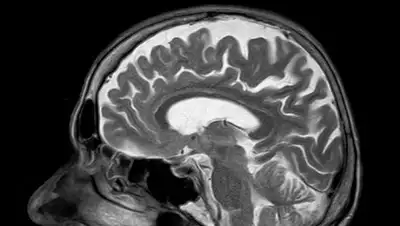

По информации ученых, рак мозга развивается из-за быстрого неконтролируемого деления клеток: нейронов, глиальных клеток, астроцитов, олигодентроцитов или эпендимальных клеток, которые ранее были обычными составляющими самой ткани мозга; лимфатической ткани, кровеносных кровеносных сосудов мозга, черепных нервов, мозговых оболочек, черепа, гипофиза и эпифиза.